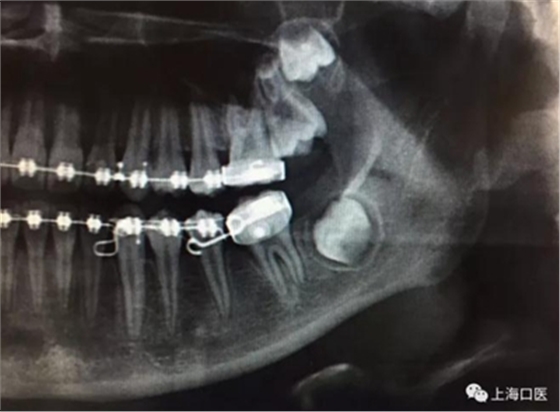

這是上海武廣增正畸工作室接診的一例非常規(guī)拔牙矯治病例,患者女性,初診年齡14歲。LL6殘冠拔除。LL7近中平移取代LL6,我們上傳了該患者一組下頜磨牙近中平移連續(xù)矯治過程的正畸X線片,與正畸界朋友分享。